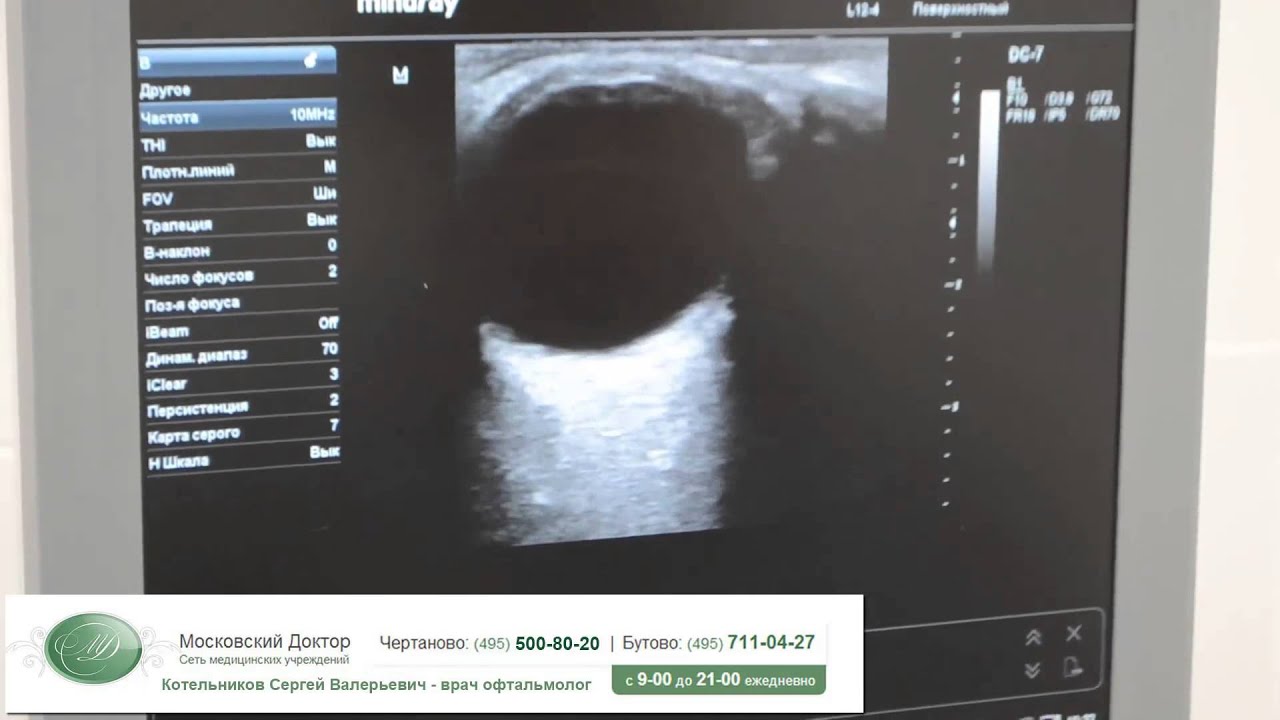

На видео УЗИ показывает отслоение сетчатки глаза: